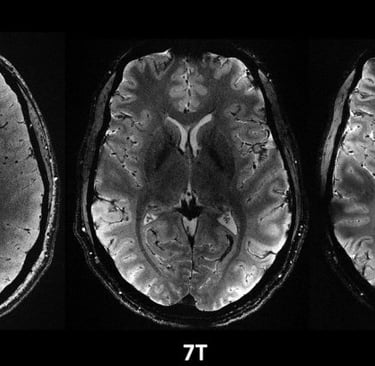

Just about four minutes. That’s all it took to acquire some of the most remarkable anatomical images of the brain from participants in the first study involving the Iseult MRI machine. The scanner, which uses magnetic resonance imaging technology, has a magnetic field intensity of 11.7 teslas, making it the most powerful in the world. The images have an impressive resolution for such a short acquisition time – 0.2 mm in-plane resolution and 1 mm slice thickness, which represents a volume equivalent to a few thousand neurons. For comparison, the same image quality would require hours with MRI scanners currently available in hospitals (1.5 or 3 teslas). This is not realistic in practice as patients would not be comfortable and any movement would “blur” the image.